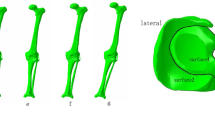

Knee joint CT image data in DICOM format were imported into Mimics software (version 16.0, Materialise NV, Leuven, Belgium). A three-dimensional model of femur, tibia, and fibula was built based on the gray value of the tissue and segmentation of the region. Subsequently, knee joint MRI image data were used to construct the ligament-cartilage model, and the MRI axial T2WI (T2-weighted image) data to construct the anterior-posterior cruciate ligament model and the medial-lateral collateral ligament model. The MRI sagittal T1WI (T1-weighted image) data were adopted to construct the medial-lateral meniscus model, and MRI sagittal T2WI image data the femoral-tibia cartilage model. And then these models were exported as a stl format file (Fig. 1) and were incorporated into Geomagic Studio software (version 11.0, Geomagic Corporation, USA) for smoothing, meshing, and fitting surface processing and also incorporated into the Solidworks software (version 2014, Dassault Systemes, S.A., USA). The ligaments, cartilage, meniscus, tibia, and tibia models were assembled as a knee joint model in the Solidworks software (Fig. 2a). The ligaments were solid element and possessed compression and extension functions.

Establishment of PFO models

Ten knee joint models were imported into the Solidworks software. About 2–3 cm tibial segments were cut at 6–10 cm below the head of the fibular to generate PFO models (Fig. 2b) [13].

The model of the before PFO contains 53,256 nodes and 1,73,214 elements, and the model of after PFO has 49,359 nodes and 1,12,258 elements. The von Mises stress distribution in the knee reflected changes in stress pathways before and after PFO. Prior to PFO, both the tibia and fibula were loaded while the tibia was loaded much more than the fibula. Before the PFO, both the tibia and fibula were loaded while the tibia was loaded much more than the fibula. However, only the tibia was loaded after the surgery (Fig. 3). Stress distribution patterns of femoral cartilage, meniscuses, tibial cartilages, and tibial plateau before and after PFO were illustrated in finite element stress nephogram. It was found that the area of stress distribution in the medial femoral cartilage was larger than that in the lateral femoral cartilage. Stress in the femoral cartilage was reduced after PFO (Fig. 4). The area of stress distribution in the medial meniscus was larger than that in the lateral side preoperatively. After PFO, stress in the medial meniscus decreased (Fig. 5) but that in the lateral side increased (Fig. 6). Furthermore, stress in the medial tibial cartilage was reduced (Fig. 7) and that in the lateral tibial cartilage increased after the surgery (Fig. 8). The maximum stress loaded on the medial side of the cortical bone after PFO was lower than that before the surgery. Before the PFO, the stress on the medial side of the tibial plateau was greater. However, the medial stress on the tibial plateau decreased and the lateral stress increased after the PFO. The stress distribution in the cortical bone of the tibial plateau showed that stress was transferred from the medial area to the lateral area after the surgery (Fig. 9).